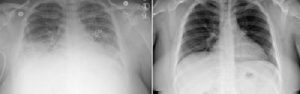

Rätselhafte Krankheitsfälle unter Vaping-Konsumenten: Eine Form der Lipidpneumonie?12. September 2019 Lipid-geladene Makrophagen bei Patienten mit Vaping-assoziierter Atemwegserkrankung. Ölige Lipide rot eingefärbt. (Foto: © Andrew Hansen, MD, Jordan Valley Medical Center) Mediziner haben ein zuvor nicht erkanntes Merkmal derjenigen Atemwegserkrankung identifiziert, die in den vergangenen Monaten in Clustern in den USA aufgetreten ist. In der Lunge dieser Patienten befinden sich große Immunzellen, die zahlreiche ölige Tröpfchen enthalten: Lipid-beladene Makrophagen. Dank dieser Erkenntnis können Mediziner nun das Syndrom schon im Frühstadium diagnostizieren und zu einem früheren Zeitpunkt mit der richtigen Therapie beginnen. Die neuen Forschungsergebnisse könnten auch Hinweise auf die Ursachen der neuen und rätselhaften Erkrankung geben. Die Forscher von der University of Utah Health berichteten darüber im „New England Journal of Medicine“. „Es ist zwar noch zu früh um sicher zu sein, dass diese mit Lipiden beladenen Makrophagen bei der Diagnose oder dem Ausschluss dieser Erkrankung helfen“, sagt Dr. Scott Aberegg, Pneumologe und Intensivmediziner sowie Seniorautor der Studie. „Sie können helfen zu verstehen, was diese Krankheit verursacht“, fügt er hinzu. In der Bildgebung präsentiert sich die Lunge von Patienten mit der „Vaping-Krankheit“ wie bei einer schweren viralen oder bakteriellen Pneumonie. Tests auf eine solche Erkrankung verliefen allerdings negativ. Stattdessen beruht die Diagnose auf dem Ausschluss bekannter Ursachen für ähnliche Atemwegserkrankungen in Verbindung mit dem Wissen, dass der Patient in der Vergangenheit gedampft hatte. Links: Lungen-Scan eines von der Vaping-assoziierten Atemwegserkrankung schwer betroffenen Patienten. Rechts: Lungen-Scan desselben Patienten nach Behandlung und Besserung. (Foto: © University of Utah Health) Die Forscher identifizierten die mit Lipiden beladenen Makrophagen bei sechs von sechs Fällen am University of Utah Hospital in Salt Lake City, die zum Zeitpunkt der Einreichung der Ergebnisse zur Veröffentlichung aufgetreten waren. Die Zellen wurden in bronchoalveolärer Lavage gefunden. Durch Anfärben mit einem Farbstoff namens Oil-red-O wurden die öligen Tröpfchen sichtbar. Aberegg: „Diese Zellen sind sehr charakteristisch, und wir sehen sie nicht oft. Das hat alle dazu veranlasst, intensiv darüber nachzudenken, warum sie dort waren. Reinigen sie die Lunge von Rückständen des Vapings?“ Die Mediziner führten den Test im Juli 2019 an dem ersten an der University of Utah Health behandelten Patienten durch, nachdem der überweisende Arzt vermutet hatte, dass der Patient an einer Lipidpneumonie leiden könnte. Diese Erkrankung wird diagnostiziert, indem man den Patienten auf Lipid-beladene Makrophagen screent. Nachdem der Marker bei diesem Patienten gefunden worden war, führten die Ärzte bei nachfolgenden Patienten, bei denen der Verdacht auf eine Vaping-Krankheit bestand, denselben Test durch. Alle hatten einen positiven Befund. Seit dem Einreichen der Ergebnisse zur Veröffentlichung ist die Zahl der Fälle von Vaping-Krankheit mit Lipid-beladenen Makrophagen auf zehn von zehn untersuchten Patienten angestiegen. Wöchentlich kommen neue Fälle hinzu. Es bleibt die Frage, ob die Vaping-Krankheit eine Art der Lipidpneumonie darstellt. Trotz Ähnlichkeiten gibt es auch Unterschiede. Im Gegensatz zur Vaping-Krankheit tritt eine klassische Lipidpneumonie typischerweise bei älteren Personen auf, die normalerweise durch versehentliches Einatmen von Laxanzien auf Ölbasis verursacht wird. Die klassische Lipoidpneumonie stellt sich auch bei Röntgenaufnahmen der Lunge anders dar. Zusätzliche Tests müssen durchgeführt werden, um festzustellen, ob die Vaping-Krankheit als eine neue Art von Lipidpneumonie eingestuft werden kann. „Wir müssen feststellen, ob diese Zellen für die Krankheit spezifisch sind oder ob sie auch bei Patienten auftreten, die nicht krank sind und keine Symptome aufweisen. Wenn sie nur bei erkrankten Patienten auftreten, können wir damit beginnen, Zusammenhänge herzustellen zwischen dem, was wir in den Lipid-beladenen Makrophagen sehen, und Komponenten der Vaping-Öle, die dieses Syndrom verursachen könnten“, sagt Aberegg.